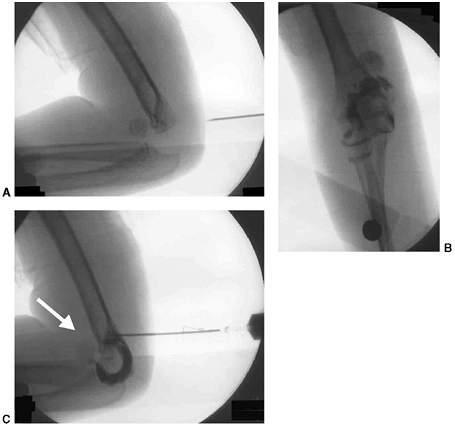

displaced. Treatment begins with a complete assessment of perfusion and

nerve function. Neurovascular problems are frequent, and fracture